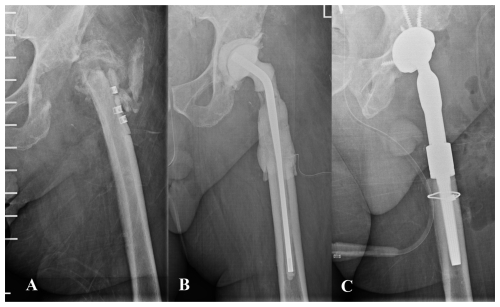

https://jbji.copernicus.org/articles/11/43/2026/jbji-11-43-2026-f03

Figure 3(A) Anteroposterior pelvic radiograph of a patient with chronic prosthetic joint infection of the left hip. The patient had previously undergone multiple procedures involving osteosynthesis material. Both the patient's medical history and the diffuse radiographic appearance of the proximal femur suggested bone involvement compatible with osteomyelitis. (B) A wide resection of the proximal femur was undertaken, and a preformed spacer was implanted. Histological analysis revealed mild neutrophil infiltration and chronic inflammatory changes within trabecular bone and bone marrow, consistent with osteomyelitis. (C) Hip reconstruction was subsequently performed using a megaprosthesis owing to the substantial bone loss in the proximal femur. This procedure may also be undertaken in a one-stage approach, although accurately determining the true extent of femoral bone involvement can be challenging.